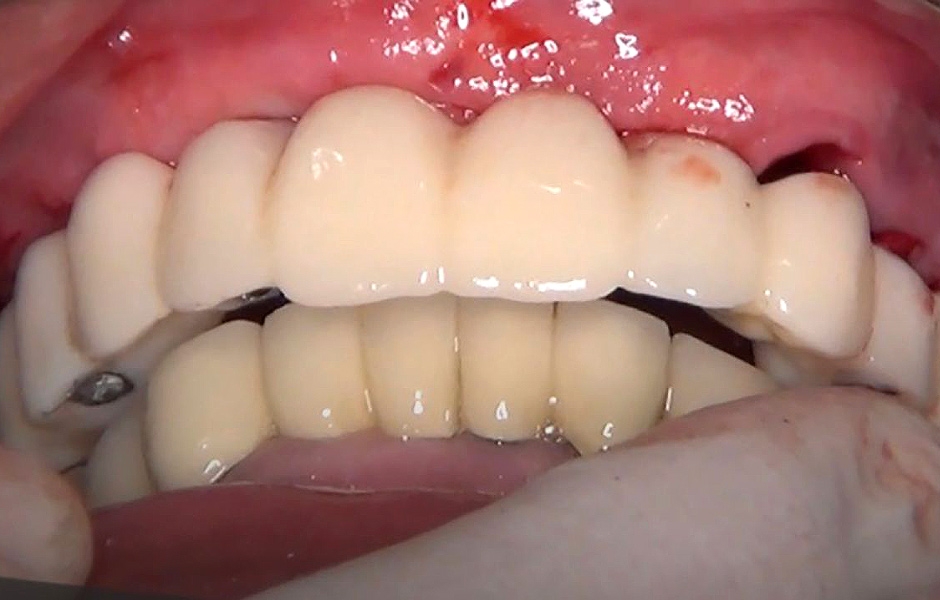

Během kontrolních návštěv pacient vykazoval výborné hojení bez pooperačních komplikací. Provizorní náhrada poskytovala optimální stabilitu a přesnost dosedu, což přispělo ke komfortu a funkčnosti provizorního protetického ošetření (obr. 44).

Definitivní náhrada byla nasazena a ověřena z hlediska estetiky, okluze a funkce (obr. 51–55). Panoramatický kontrolní snímek potvrdil, že všechny parametry protetického ošetření odpovídají očekávaným hodnotám (obr. 56).

Obr. 44